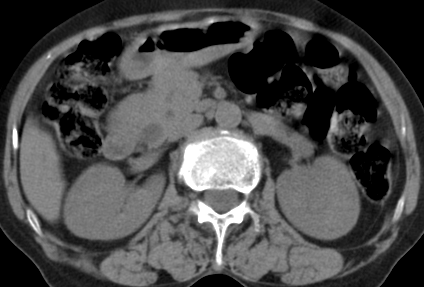

以下是引用齐原在2006-11-8 23:21:00的发言:[br]肝脏体积增大.肝表凸凹不平,肝内胆管扩张,胆总管扩张,胆总管末端突然截断,胰腺勾突增大,形态不规则.胰管扩张.考虑胰头癌.并低位梗阻性胆系扩张,胆囊炎.脾大.建议增强

以下是引用dyqct在2006-11-9 9:14:00的发言:[br]肝大,表面呈波浪状,肝内外胆管扩张,胆总管下端腔内见小结节状等密度影,胰管轻度扩张。胆囊显示不清。[br]考虑:1、胆总管下端占位性病变(等密度结石?壶腹部肿瘤?);[br] 2、肝硬化?[br] 3、建议增强扫描进一步检查。